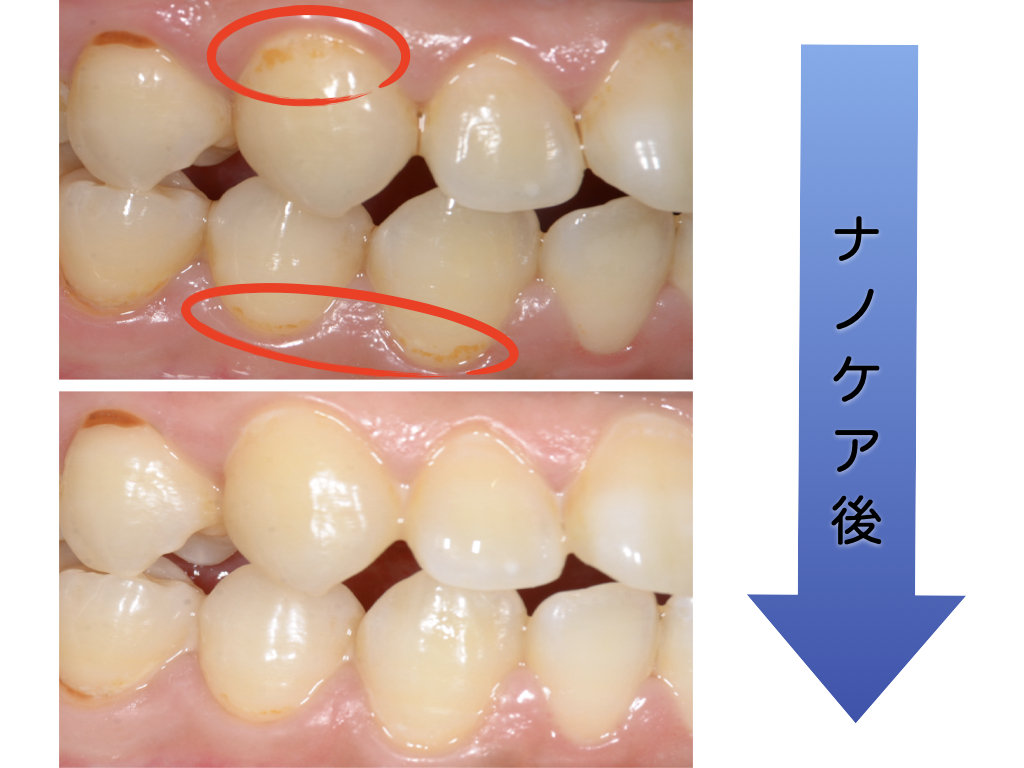

【初期むし歯を削らずに治す方法】〜衛生士によるナノケア〜|大阪(心斎橋・四ツ橋) なかやま歯科